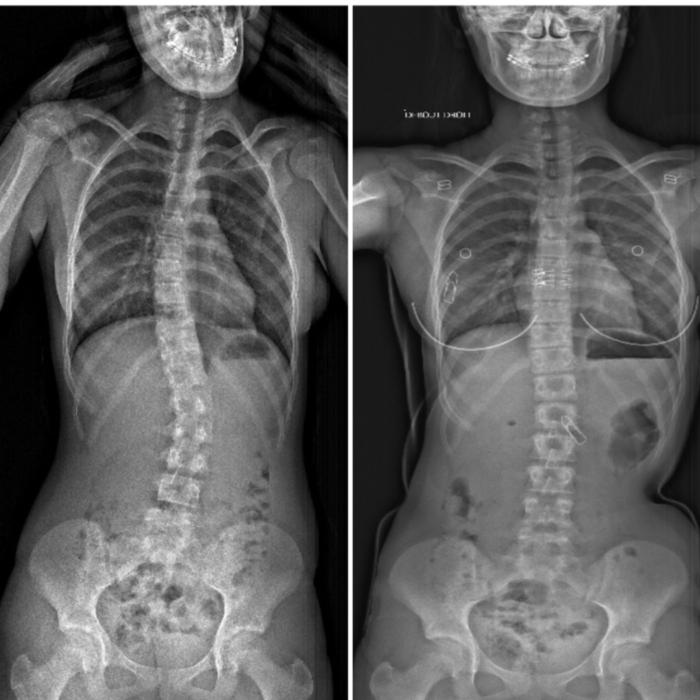

Chez l’adolescent, un corset est prescrit en cas de déformation de la colonne vertébrale évolutive (scoliose, cyphose). Le corset a pour objectif d’empêcher cette déformation de continuer à évoluer.

Exemples de corset chez l’adolescent (site corset scoliose cheneau ctm et corset scoliose 3d )